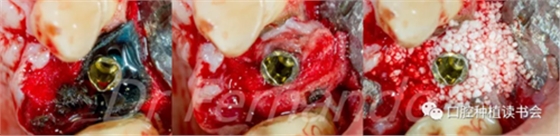

然后根據(jù)種植體周圍炎的標(biāo)準治療程序,先使用磷酸&氯己定凝膠處理種植體表面2分鐘后,接著使用抗生素溶液(透明質(zhì)酸鈉哌拉西林他唑巴坦)處理5分鐘,然后使用Cerasorb ?M 骨粉植骨(Curasan?-科盧森)(圖 21)。

圖21 機械&化學(xué)凈化種植體表面后,使用Cerasorb ?M 骨粉植骨